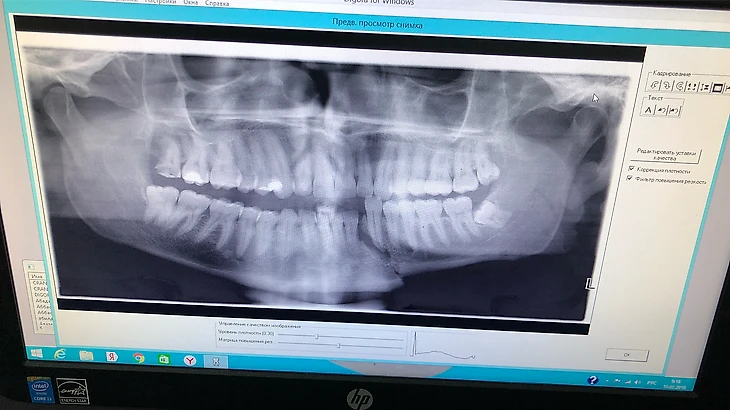

Открытый перелом челюсти со смещением, перелом кости лица правой щеки, закрытая черепно-мозговая травма, сотрясение мозга и еще много чего», – написал Ширман в инстаграме и приложил видео и фото.